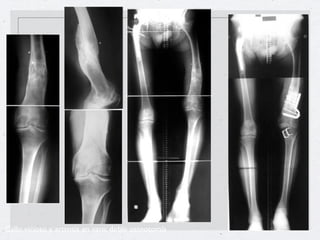

Callo vicioso en los tres planos.

Callo vicioso y artrosis en varo: doble osteotomía

Corrección de un callo vicioso de fémur

Callo vicioso enlos tres planos.

• 23.

Callo vicioso yartrosis en varo: doble osteotomía

Corrección de uncallo vicioso de fémur